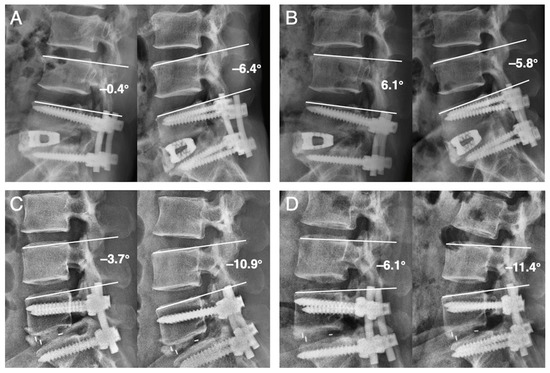

2.3. Radiological Assessment and Clinical Record

| Instability | 13 | 6 | 0.008 |

| Last FU angular m. (°) | 9.31 ± 3.31 | 7.52 ± 3.79 | 0.04 |

| Last FU angular m. (°) | 12.03 ± 4.25 | 10.09 ± 4.89 | 0.09 |